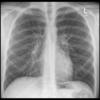

Normal PA

24 yo male

Date: 06/08/2016

Views: 6522